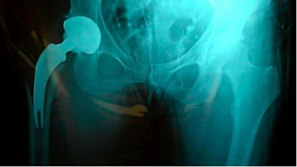

Good fit of final stem.

Stability was very impressive |

Trial neck off the final implant then 8 mm varus neck was chosen for final implantation.

Pt. doing well first day post-op. Saving all the lateral structures was very impressive.

In both of these cases with tight fit cortical bone needs to be shaped to fit the medial curve and preparations for the differential size between the rasp and implant with the T-back. More experience is needed but possible additional preparation for the definitive stem in very tight situations may need to be addressed. Over all impression was good and basic instruments work well and the initial stability of the implant is impressive.